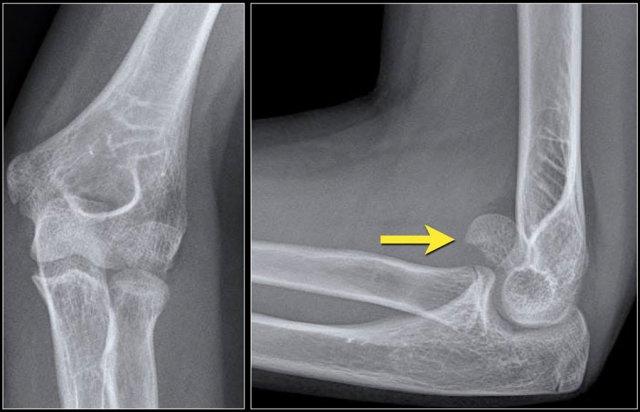

Normal medial epicondyle projecting posteriorly. Notice radial head dislocation and olecranon fracture

Medial Epicondyle avulsion

Mỏm trên lồi cầu trong là một mấu xương vì nó không đóng góp vào sự tăng trưởng theo chiều dọc của xương cánh tay.

Nó nằm ở phía sau của khuỷu tay.

Trên hình chiếu thẳng bên, đặc biệt nếu cánh tay ở tư thế xoay trong, nó có thể chiếu ra phía sau đến mức có thể gợi ý một tổn thương bong điểm bám (hình ảnh).

Tuy nhiên, các tổn thương bong điểm bám thường nằm ở vị trí xa hơn và phía trước hơn.

Do mỏm trên lồi cầu trong là cấu trúc ngoài khớp, gãy xương hoặc bong điểm bám sẽ không tự động tạo ra dấu hiệu đệm mỡ dương tính.